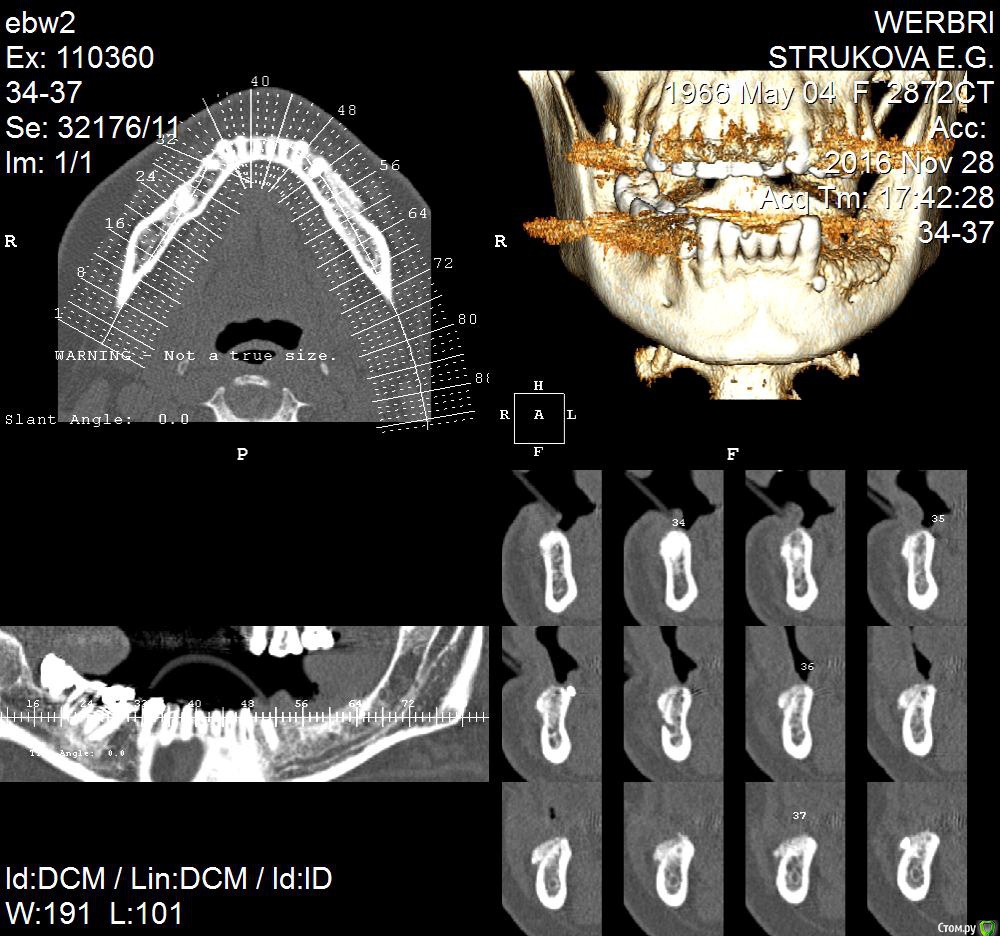

kamranchick Опубликовано 25 апреля, 2016 Поделиться Опубликовано 25 апреля, 2016 Пациентка обратилась с целью восстановления жевательного отдела.финансовый вопрос не интересует, хотелось бы чтобы с минимальными рисками.1.я думаю - удаление, 3 винта, сосидж, 5 пинов.чтобы вы предложили? Ссылка на комментарий

kamranchick Опубликовано 2 мая, 2016 Автор Поделиться Опубликовано 2 мая, 2016 ну я указал 3 сегмент, 3 винта, следовательно удаление 5 го зуба, установка имплантатов в область 35 36 и 37 Ссылка на комментарий

dantist_movani Опубликовано 2 мая, 2016 Поделиться Опубликовано 2 мая, 2016 ну я указал 3 сегмент, 3 винта, следовательно удаление 5 го зуба, установка имплантатов в область 35 36 и 37 так там и так 3.5 нет. Ссылка на комментарий

dantist_movani Опубликовано 2 мая, 2016 Поделиться Опубликовано 2 мая, 2016 Ось имплантата в проекции 3.7 слишком язычная, так же имплантат устанавливали? Ссылка на комментарий